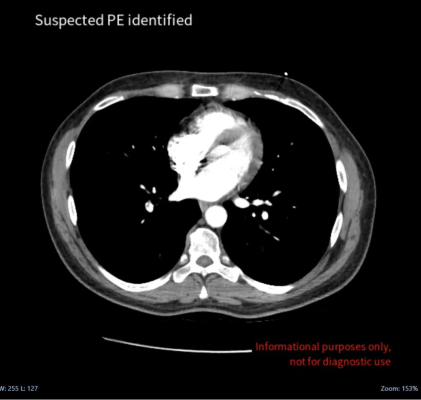

February 22, 2023 — Medical imaging AI specialist Avicenna.AI announced the launch of CINA-iPE, a CE-marked AI tool that analyzes images from chest CT scans for the presence of incidental pulmonary embolism. CINA-iPE is the first tool in CINA Incidental, a new suite of medical imaging solutions from Avicenna.AI that detect unsuspected pathologies on CT scans.

Incidental pulmonary embolism is a frequent finding on routine CT scans of the chest, but only 25% of incidental emboli are reported at the initial interpretation. Delayed and missed findings are some of the most serious problems in diagnostic imaging, and incidental pulmonary embolism is a significant cause of mortality in the cancer patient population.

“If pathologies are visible on a CT scan, the technology now exists to detect them – helping clinicians reduce time-to-treatment and save lives,” said Cyril Di Grandi, co-founder, and CEO of Avicenna.AI. “Our CINA Incidental suite helps healthcare professionals detect incidental findings in patients receiving imaging for entirely different health conditions, improving patient care and outcomes. The launch of CINA-iPE is the first step in a new direction for Avicenna.AI. Pulmonary embolism is a dangerous, life-threatening condition, and with CINA-iPE we hope to increase the number of patients identified with incidental PE and help improve their outcomes.”